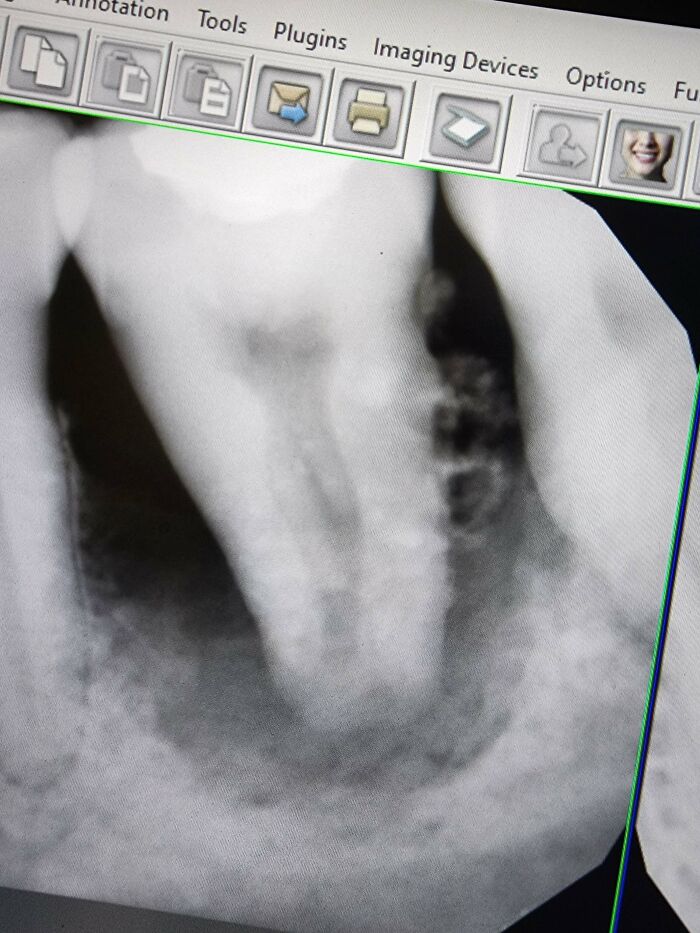

These Are Mulberry Molars, Which Are Associated With Congenital Syphilis